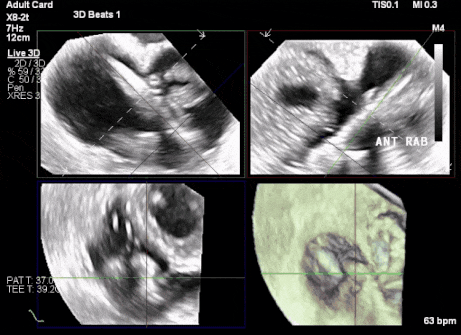

1、患者左心機械瓣術后,術中TEE成像有偽影干擾;2、三尖瓣重度反流,右心房、心室嚴重擴張致三尖瓣葉拴系,Gap:15.3mm,注意阻擋件抓取瓣葉操作。

術前超聲顯示三尖瓣重度反流合并拴系